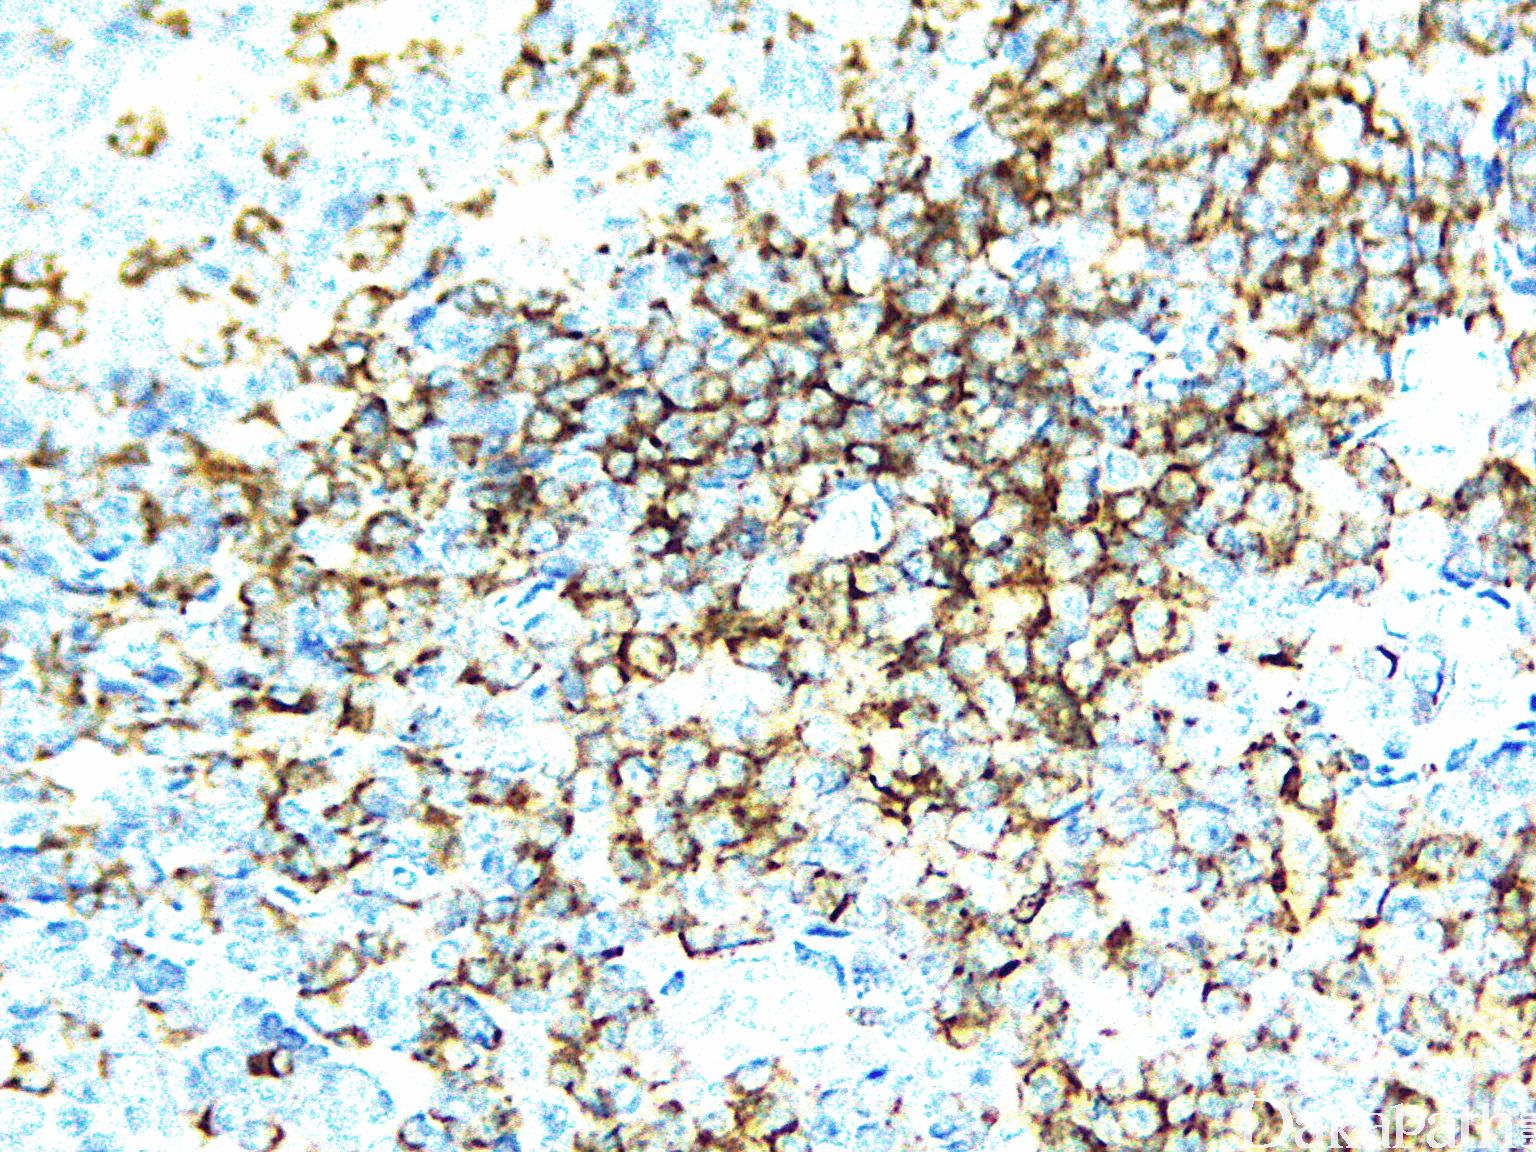

广谱且较稳定的全 T 细胞抗原,表达于成熟 T 细胞及胸腺细胞,也可表达于 NK 细胞,用于 T 细胞及 NK 细胞来源肿瘤的诊断与鉴别。

信号定位: 细胞膜

- T cell marker (membranous staining), although CD3 is more commonly used